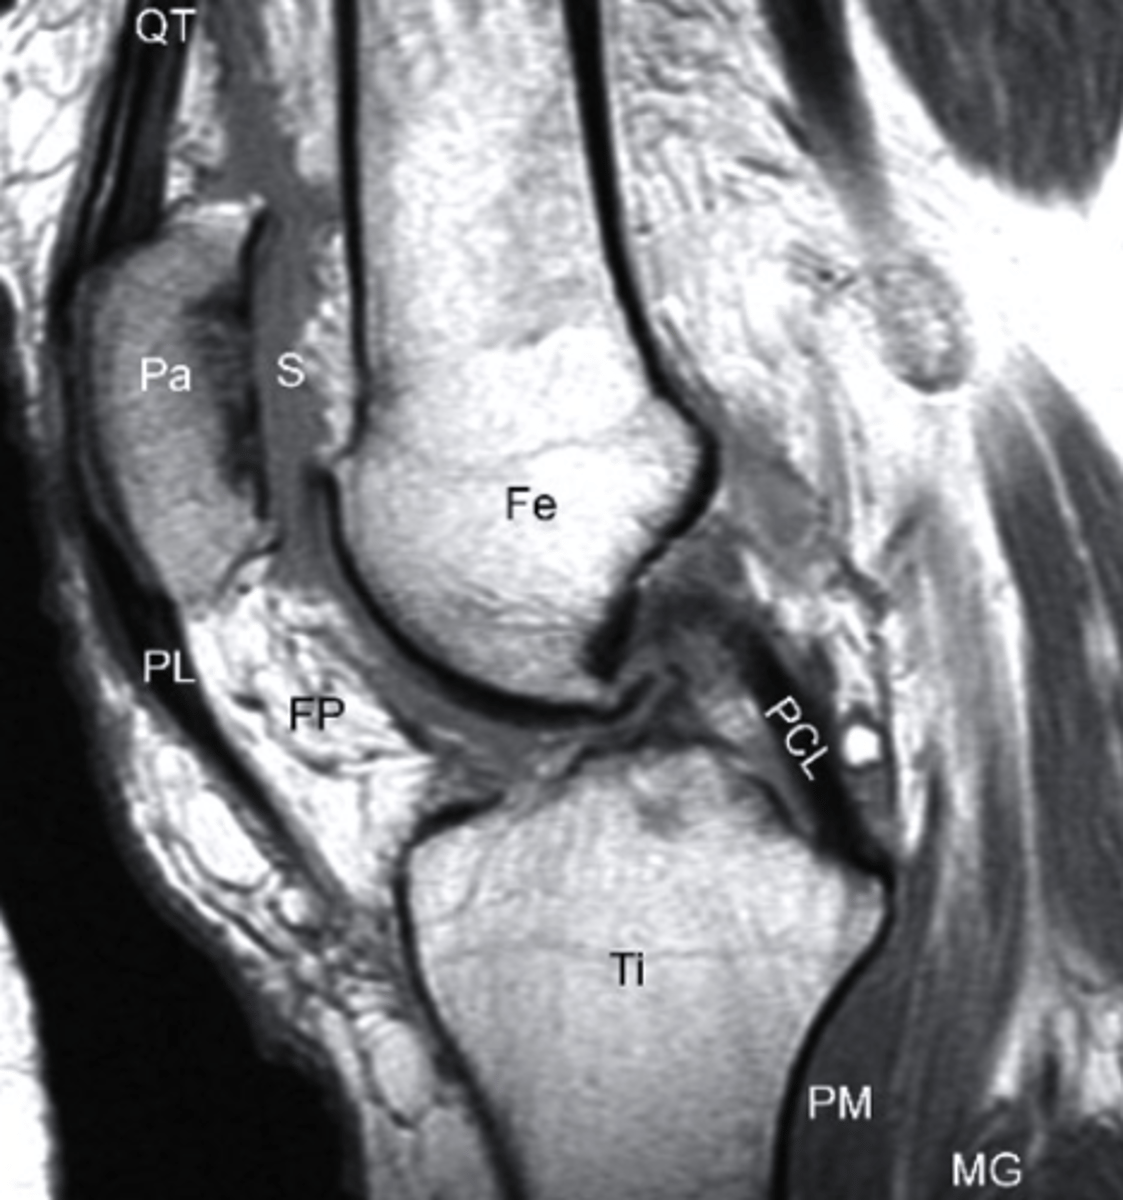

T2 MRI

what type of imaging is this?

a. T2 MRI

b. CT Scan

c. Radiograph

d. T1 MRI

Synovial Fluid, T2 MRI

what does the S represent on this image and what type of image is this?

a. Swelling, T1 MRI

b. Sclerosis, T1 MRI

c. Synovial Fluid, T2 MRI

d. Sartorius, T2 MRI

sagittal

what is the view of this image?

a. coronal

b. axial

c. frontal

d. sagittal